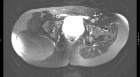

J.R. - 45 year old female with large buttock mass

Zoom image: Radiological image Radiological image.